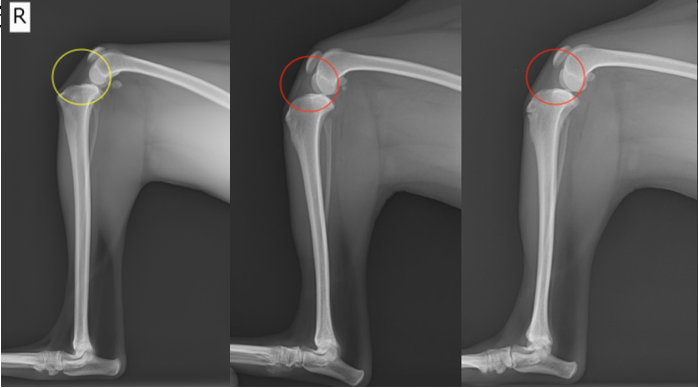

左側)健常な肢:膝蓋骨・膝蓋靱帯の下に膝蓋下脂肪体が存在 中央・右側)免疫介在性関節炎症例の肢:関節包の腫脹により膝蓋下脂肪体が圧迫されている所見(Fat Pad Sign)